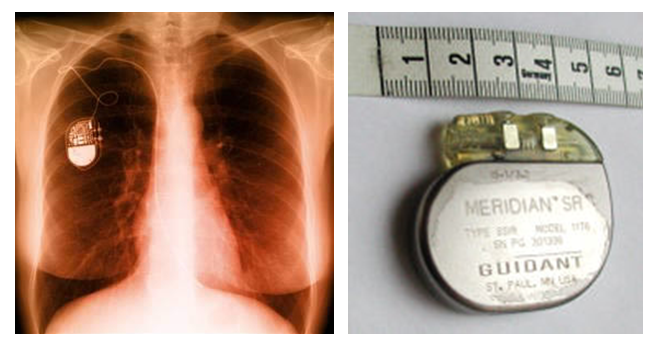

Figura 3 - Imagem de um marcapasso implantado em uma pessoa

Uma aplicação importante que está sendo proposta é para os usuários de marcapasso (dispositivo que regula os batimentos do coração por estímulo elétrico e, atualmente, é implantado no corpo do paciente e alimentado por baterias).

A ideia é colocar o chipe nas proximidades dos pulmões que, através de seu movimento natural e contínuo ao longo da respiração, seria capaz de gerar energia e manter o dispositivo ativo. Atualmente, a única forma de substituir a bateria do marcapasso envolve uma cirurgia.

Os pesquisadores tiveram o cuidado de fazer o chipe com materiais que o corpo humano não rejeita. O estudo de novos materiais para implantes em seres humanos é uma área em grande desenvolvimento e que requer bastante conhecimento de química.